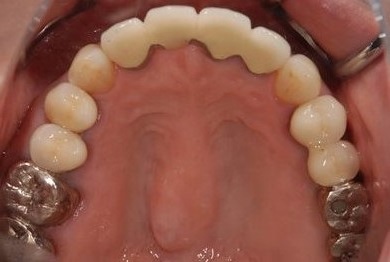

インプラントの症例写真 IMPLANT

骨再生スピードインプラント治療+セラミック治療

| 治療内容 | インプラント3本(抜歯即日スピードインプラント、GBR)、メタルボンドセラミッククラウン4本 | ||||||||||||||||||||||||||||||||

| 総治療費 | 1,509,902円 | ||||||||||||||||||||||||||||||||

| 治療期間 | 1年5ヶ月 |